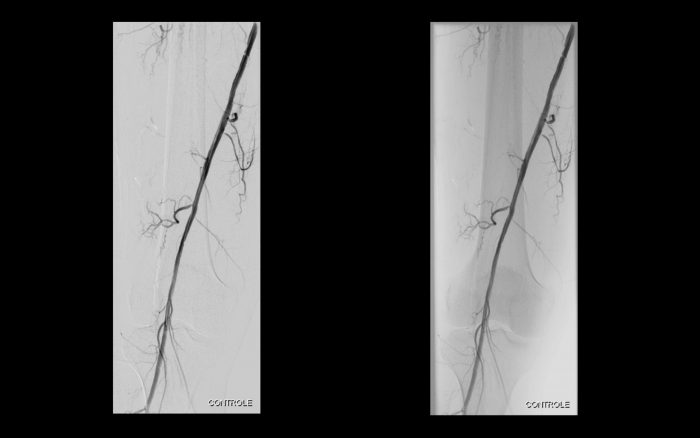

Paciente com história de claudicação dos membros inferiores para curtas distâncias, já submetido a angioplastia do membro inferior direito, retorna ao serviço com piora dos sintomas no lado esquerdo, sem lesão trófica (Rutherford 3)